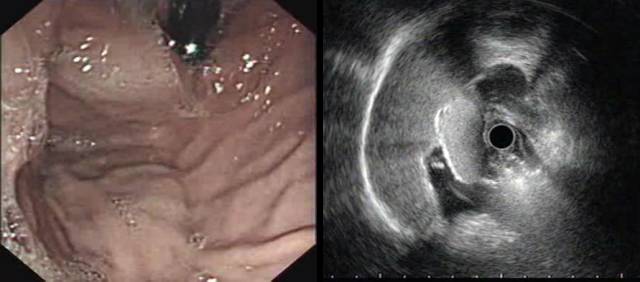

下面病例我们可以看到胃底粘膜下隆起,中央有凹陷(图A),外院CT也考虑胃底间质瘤(图B白色箭头处)。

患者拟手术来我院行超声内镜检查,小探头发现局部胃壁结构欠清,肿块内部为均匀点状回声(图 A),改环扫EUS探查见肿块后方为膈肌,内部为均匀点状回声,考虑副脾,该患者10年前因外伤切除脾脏,故诊断为脾脏切除后副脾代偿性增生外压。

嘱咐患者在我院复查CT检查,请放射科同事局部放大并重建后证实为副脾,故放弃手术。

经典EUS教课书上强调用胃壁五层结的完整性来判断外压,但胃底需倒镜探查,EUS扫描平面很难垂直于病灶且信号衰减明显,识别五层结构困难。此时,观察重点应是病灶的内部回声特点,小间质瘤内部为均匀低回声,这和副脾的点状回声完全不同。打个比方,如果让你分辨一只小老虎(间质瘤)和一个家猫(副脾),你可以通过步态和皮毛来判断(相当于观察胃的五层结构),也可以试图掐一下它们,如果发出“瞄”的声音就是家猫(相当于观察病灶内部的回声特点),下面的病例也是通过上述方法诊断为副脾。

该患者也有脾切除病史,胃镜发现胃底隆起,小探头超声见卵圆形病灶,后方膈肌,内部为典型的均匀点状回声,故诊断副脾,从上述两个病例可以看到,如碰到脾切除后的胃底粘膜下隆起,一定要有副脾增生外压的意识。